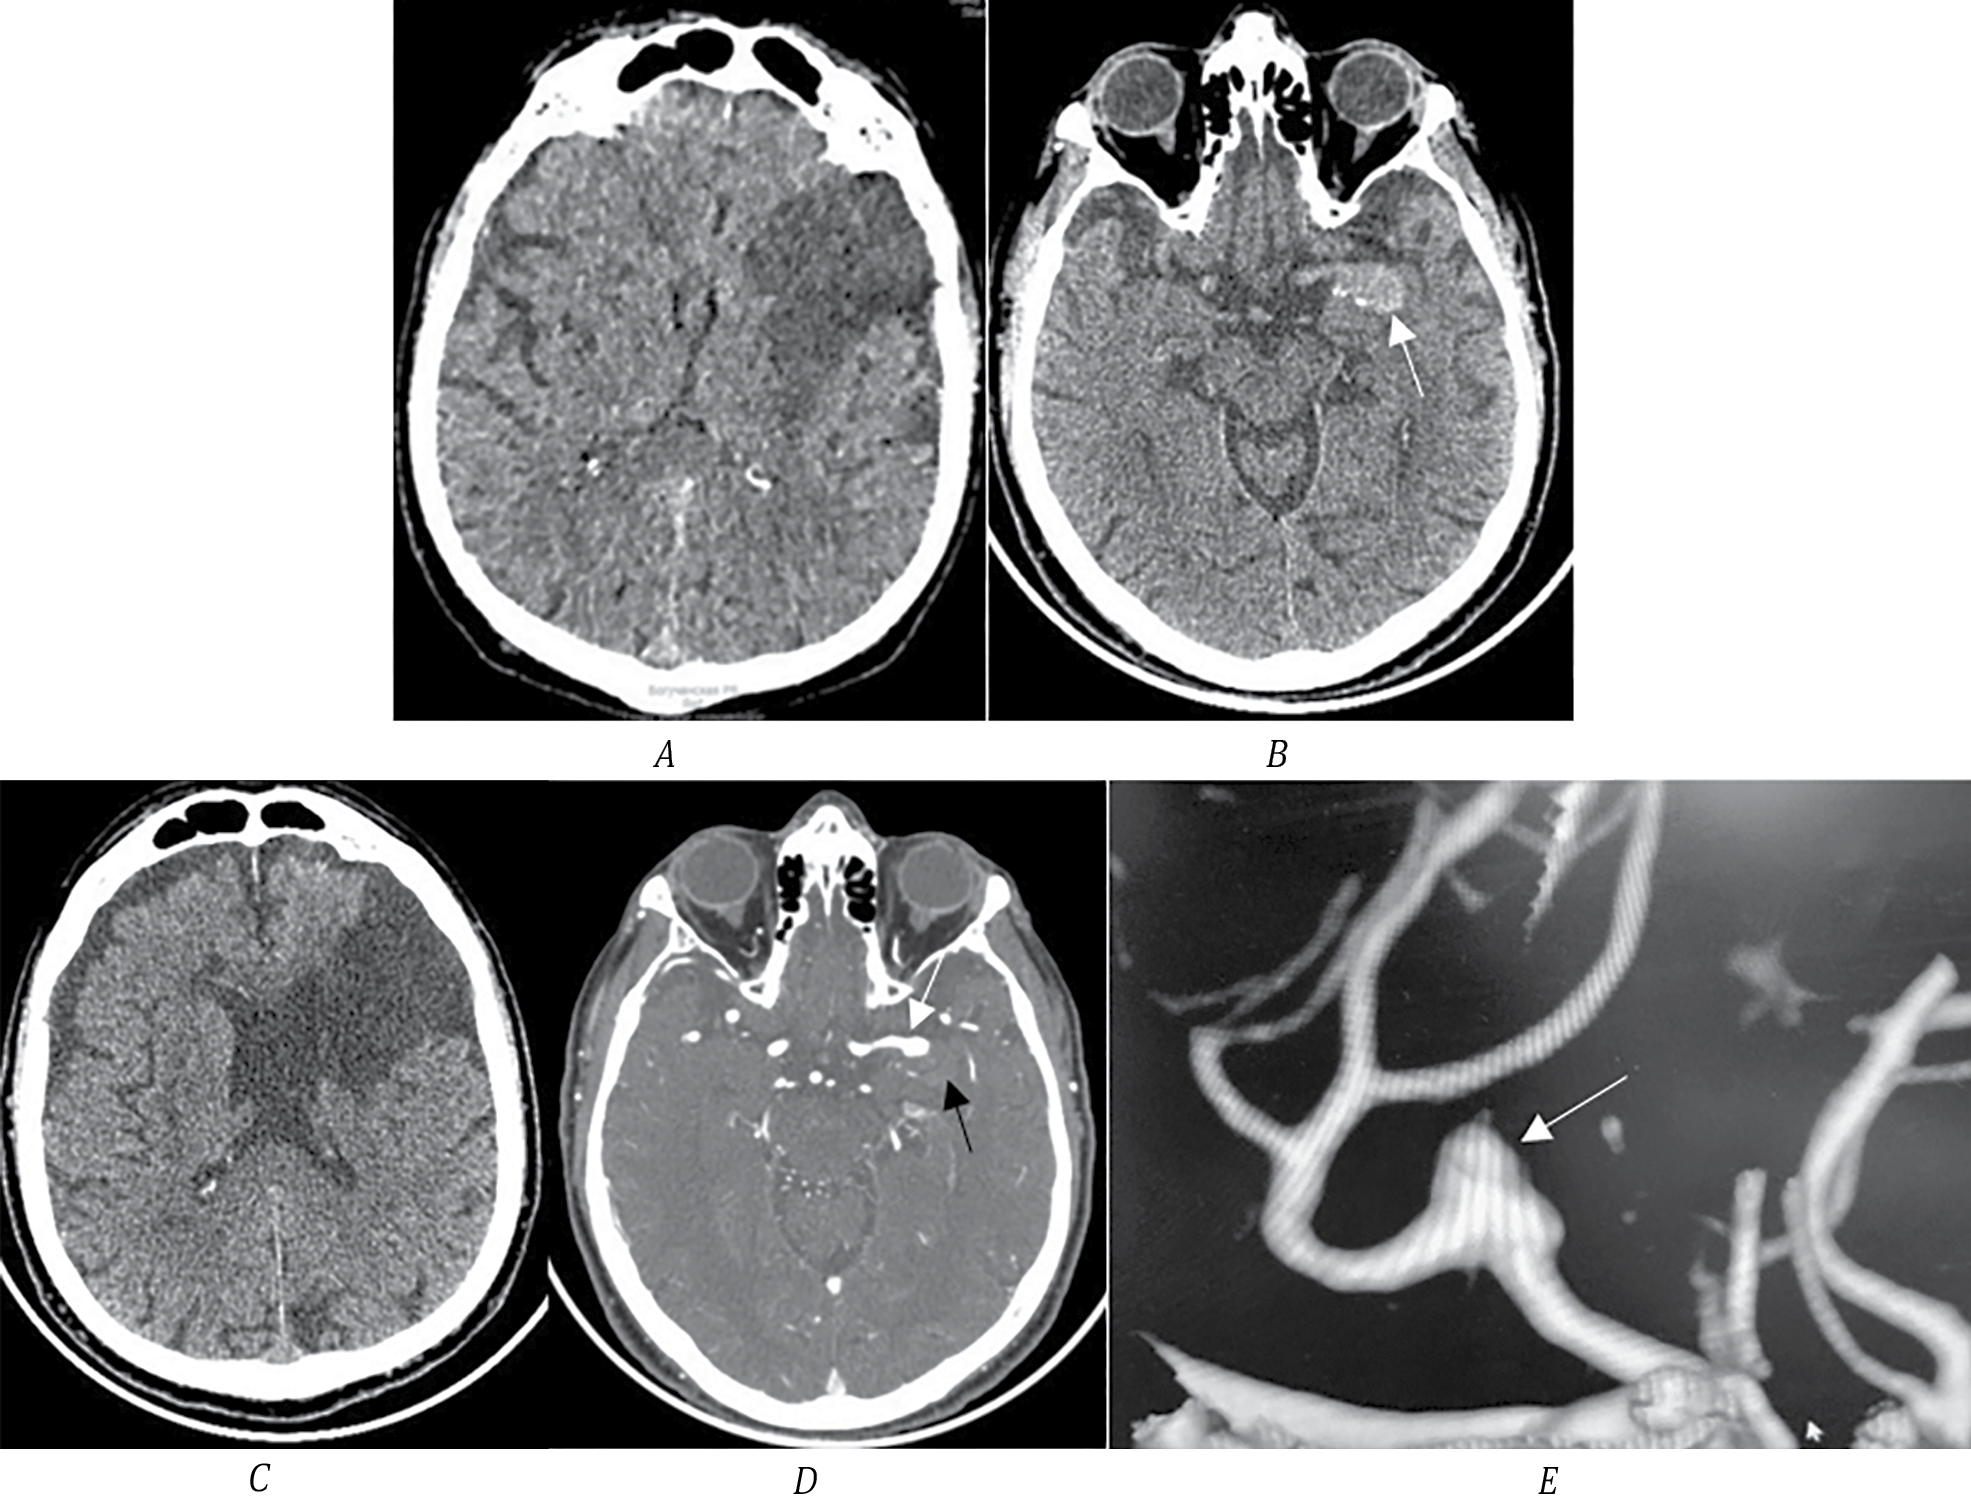

В приёмный покой доставлен пациент А., 24 года, с остро развившейся правосторонней гемиплегией. Выполнено МСКТ головного мозга: выявлен участок повышенной плотности в хиазмально-селлярной области слева, который необходимо дифференцировать как очаг кровоизлияния или ТА ВСА (рис. 4, А). По МСКТ-ангиографии определяется небольшая функционирующая часть аневризмы левой ВСА. ВСА и СМА слева проходимы на всём протяжении.

Рис. 4. МСКТ головного мозга пациента А.

А — стрелкой указана ТА левой ВСА; B — МСКТ-ангиография, 3D-реконструкция, стрелкой указана функционирующая часть аневризмы левой ВСА; C — МРТ головного мозга, Т1-ВИ, стрелкой указана ТА левой ВСА; D — МРТ в режиме DWI, зоны острой ишемии — в подкорковых структурах левого полушария головного мозга.

Выполнено МРТ головного мозга. Определяется ТА левой ВСА размером 15 мм. В режиме DWI определяются зоны острой ишемии (ограничения диффузии) в области головки хвостатого ядра справа, скорлупы, коры островка, латеральных и медиальных отделов правой лобной доли. С учётом такого многоочагового характера ишемии и наличия ТА ВСА наиболее вероятно, что эмболия из мешка тромбов привела к формированию множественных зон ишемии. Других факторов риска ИИ у молодого пациента не выявлено. Неврологический статус пациента оценён в 11 баллов по NIHSS. В плановом порядке выполнено микрохирургическое клипирование аневризмы ВСА. Пациент выписан с функциональным статусом на уровне 2 по модифицированной шкале Рэнкина.